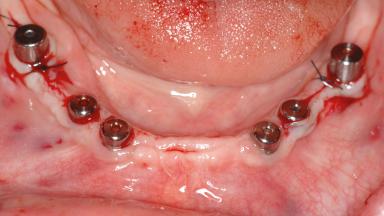

Le Fort I Interpositional Graft and Mandibular Sandwich Osteotomy for Maxillofacial Rehabilitation after Severe Periodontitis

A 47-year-old woman who had suffered from aggressive periodontitis requiring a number of periodontal interventions over more than 10 years was referred by her general dental practitioner and periodontologist for bone augmentation and implant therapy. Her failing dentition had already been scheduled for extraction. The patient expressed a desire for implant-supported fixed restorations and esthetic improvement of her lower face. She had agreed to consult with a maxillofacial surgeon after the referring dentist had suggested bone augmentation. An initial examination by the maxillofacial surgeon revealed mobility of all residual teeth in a patient who was very unhappy with the function of her removable partial dentures. Due to periodontally migrated flaring teeth and loss of occlusal support, the vertical dimension of occlusion was dramatically reduced. The patient was displeased with her lower face because of deepened nasolabial, commissural, and supramental folds.

# of Implants 14

Bone Augmentation Horizontal|Sinus Floor Elevation|Staged|Vertical

Augmentation Materials Autogenous chips|Autogenous block(s)|Xenogenous|Membrane